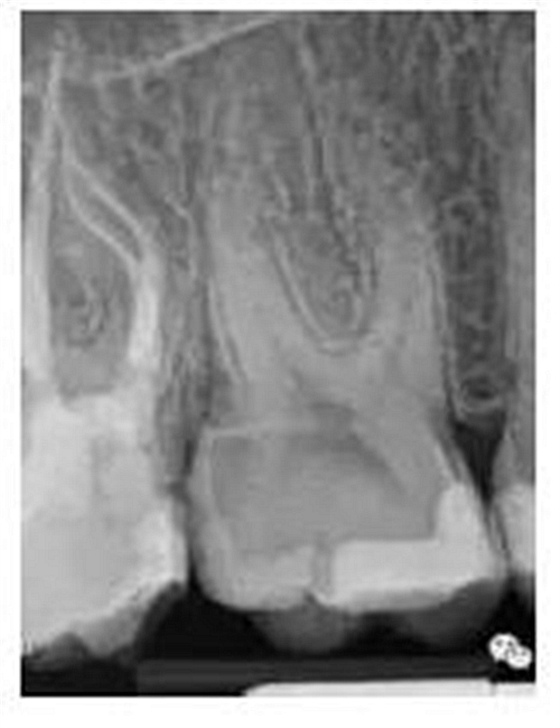

最后來玩一個(gè)根管治療質(zhì)量的評(píng)估——下圖是武大彭彬教授的一個(gè)病例,仔細(xì)觀察可以挑出一點(diǎn)問題,但問題事出有因!看看你的“眼力”如何——問題在那里?教授的專業(yè)水平是不用懷疑的,那么事出的原因可能是什么?

問題答案:這個(gè)病例的問題主要反應(yīng)在開髓的洞形修整,注意觀察該牙X-RAY的左側(cè)洞壁,如果常規(guī)情況制備成這樣是由于裂鉆破壞了洞壁和洞底所形成的臺(tái)階。如果評(píng)估根管治療的質(zhì)量那是要扣分的!但這個(gè)病例仔細(xì)觀察洞壁形態(tài)就可以看出:該病例屬于再治療的病例,因此還是屬于一個(gè)理想的病例。